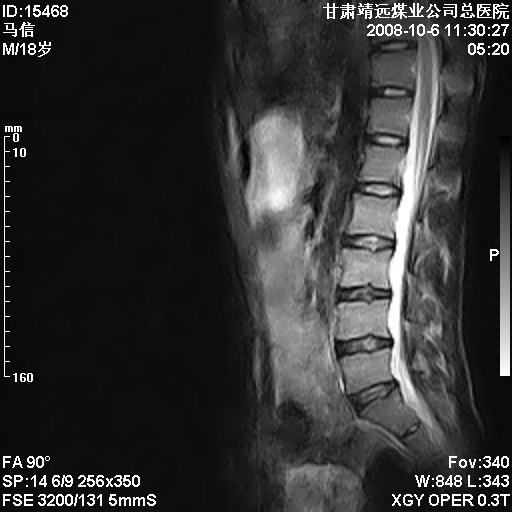

患者18岁,学生,在玩耍中受伤来检查,患者喜欢打篮球。颈椎内异常信号影,我们考虑占位,但是不像占位,又考虑硬膜囊的增厚,大家关建看颈椎椎管内的那个异常占位信号

腰椎的改变是不是正常发育的改变,还是打篮球的长期慢性损伤。

考虑 c3-4 c4-5 c5-6椎间盘突出,l3-4 l4-5 l5-s1椎间盘变性

颈椎建议做增强扫描;腰椎诸椎终板骨骺炎。

后纵韧带增厚,颈2/3、3/4、4/5、5/6椎间盘变性、突出;椎体有旋转,提示椎小关节有问题;腰椎间盘变性,许莫氏结节。

后纵韧带增厚,颈2/3、3/4、4/5、5/6椎间盘变性、突出;椎体有旋转,提示椎小关节有问题。腰椎诸椎体终板骨骺炎可能性大!支持!